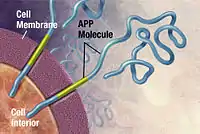

Alzheimer's disease has been identified as a protein misfolding disease (proteopathy), caused by plaque accumulation of abnormally folded amyloid beta protein and tau protein in the brain.[100] Plaques are made up of small peptides, 39–43 amino acids in length, called amyloid beta (Aβ). Aβ is a fragment from the larger amyloid precursor protein (APP). APP is a transmembrane protein that penetrates through the neuron's membrane. APP is critical to neuron growth, survival, and post-injury repair.[101][102] In Alzheimer's disease, gamma secretase and beta secretase act together in a proteolytic process which causes APP to be divided into smaller fragments.[103] One of these fragments gives rise to fibrils of amyloid beta, which then form clumps that deposit outside neurons in dense formations known as senile plaques.[97][104]